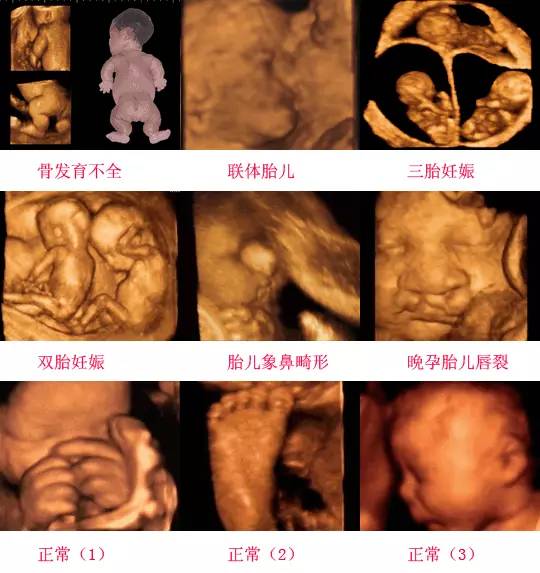

摘要:通過四維彩超技術(shù),我們能夠清晰地觀察到胎兒蛋蛋的發(fā)育情況,開啟早期胎兒生殖器官發(fā)育的探索之旅。這項(xiàng)技術(shù)能夠展示胎兒生殖器官的立體圖像,幫助醫(yī)生了解胎兒生殖系統(tǒng)的發(fā)育狀況,為早期發(fā)現(xiàn)潛在問題提供了可能。這不僅有助于保障胎兒的健康,也為優(yōu)生優(yōu)育提供了科學(xué)依據(jù)。

四維彩超是一種先進(jìn)的醫(yī)學(xué)影像技術(shù),通過實(shí)時(shí)觀察胎兒在母體內(nèi)的活動(dòng)情況,為醫(yī)生提供了豐富的診斷信息,在四維彩超下,我們可以清晰地觀察到胎兒的蛋蛋(睪丸)的形態(tài)、位置和大小等特征,胎兒蛋蛋是男性生殖系統(tǒng)的重要組成部分,對(duì)于胎兒的生長(zhǎng)發(fā)育具有重要意義。

在四維彩超下,胎兒蛋蛋呈現(xiàn)出特定的形態(tài)和外觀,通常情況下,胎兒蛋蛋呈現(xiàn)出圓形或橢圓形,表面光滑,內(nèi)部回聲均勻,隨著胎兒的發(fā)育,蛋蛋會(huì)逐漸增大,并呈現(xiàn)出明顯的性別特征,醫(yī)生可以通過四維彩超技術(shù),對(duì)胎兒蛋蛋的大小、形態(tài)和位置進(jìn)行評(píng)估,以判斷胎兒生殖系統(tǒng)的健康狀況。

胎兒蛋蛋的發(fā)育是一個(gè)復(fù)雜的過程,受到多種因素的影響,在胎兒發(fā)育的早期階段,蛋蛋位于腹腔內(nèi),隨著胎兒的生長(zhǎng)發(fā)育,蛋蛋逐漸下降至陰囊,這個(gè)過程受到激素、遺傳和環(huán)境等多種因素的影響,在四維彩超的觀測(cè)下,我們可以實(shí)時(shí)了解胎兒蛋蛋的發(fā)育過程,及時(shí)發(fā)現(xiàn)異常情況并采取相應(yīng)的治療措施。

四維彩超技術(shù)在評(píng)估胎兒蛋蛋發(fā)育方面具有重要意義,通過四維彩超,醫(yī)生可以實(shí)時(shí)觀察胎兒蛋蛋的形態(tài)、位置和大小等特征,了解胎兒生殖系統(tǒng)的發(fā)育情況,四維彩超還可以幫助醫(yī)生發(fā)現(xiàn)可能的異常情況,如睪丸未降、睪丸囊腫等,為及時(shí)采取治療措施提供依據(jù)。